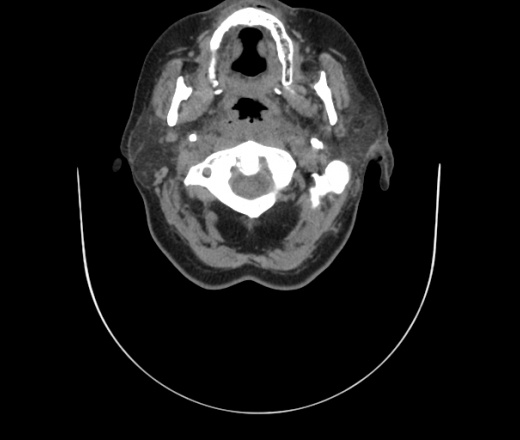

Женщина поступила в х/о спустя 4 дня после того как при употреблении карася подавилась костью.

Наличие газа в средостении на протяжении тел С2-С6 (медиастинальна эмфизема); рыбная кость на уровне тела С6.

При всем уважении, но говорить о медиастинальной эмфиземе, оценивая мягкие ткани шеи, как-то слишком резко. На мой взгляд, это ретрофарингеальное пространство.

Эвакуировали почти 100мл гноя. Но кость не смогли найти. Думаю что она даст дальнейшее ослоднение. Эндоскопически за черпалонадгортаной звязкой не смогли зайти в пищевод, все мягкие ткани отечные, просвет пищевода сдавлен. По всей видимости параэзофагеальная клетчака тоже задействована. Эмпиема, если ее можно так назвать, незнаю как правильно дошла до уровня яремной вырезки. Чем закончиться напишу. Ждем медиастинита.

Флегмона заглоточного пространства шеи, только операция, флегмоны вскрывают. Риск медиастинита.

Согласен с Вами; конечно, наличие газа в клетчатке ретрофарингеального пространства (затмение с опечаткой..). К сожалению, процесс "продвигается" к медиастиниту. Но почему никто, не отмечает наличие рыб. кости; или это для Всех очевидно?

Кость то мы сразу выявили, размеры где то 17*2мм, но ее так и не получается найти в этой каше